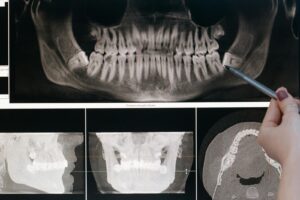

L’examen dentaire régulier comprend plusieurs aspects fondamentaux. Le praticien effectue d’abord une inspection visuelle approfondie de la cavité buccale, recherchant les signes précoces de caries, de gingivite ou d’autres pathologies. Cette étape peut être complétée par des radiographies permettant de détecter les problèmes invisibles à l’œil nu.

Les nouvelles technologies permettent aussi un diagnostic précoce plus précis. Les caméras intra-orales et les systèmes de détection des caries par fluorescence facilitent l’identification des lésions à un stade très précoce, permettant une intervention minimalement invasive. Cette approche préventive moderne limite considérablement le recours aux traitements plus lourds et coûteux.